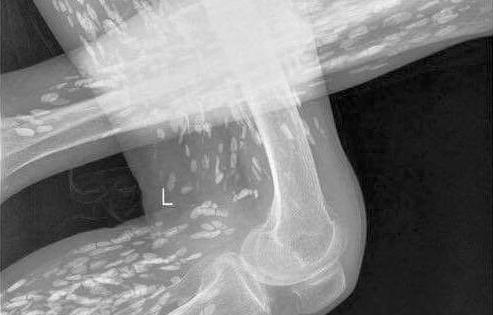

Ngứa cổ, khàn tiếng trong thời gian dài, nam thanh niên tại Bắc Giang tá hỏa khi thấy con đỉa dài 3 cm ký sinh trong cổ họng.